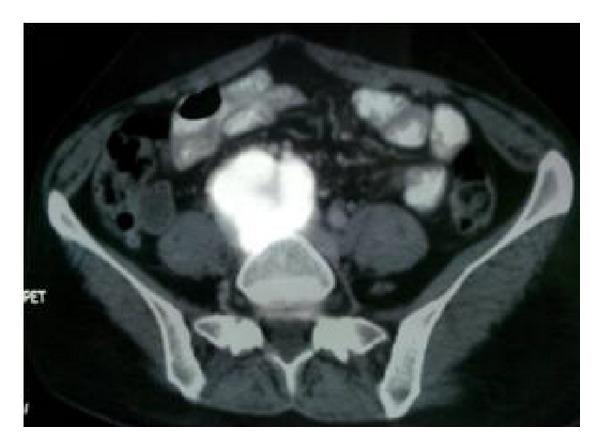

Paragangliomas are neuroendocrine tumors that arise from sympathetic nerve ganglia. They can develop anywhere from the neck to the pelvis, but are most commonly found in the abdomen, particularly at the aortic bifurcation or in the periaortic region. Malignant paragangliomas account for 29-40% of cases. We report a case of 36-year hypertensive female presented with and right flank pain and accelerated hypertension. On evaluation she was diagnosed to have non unctioning kidney due to malignant pelvic paraganglioma with right ureteric encasement. We believe our case is one of the first reported in literature as rare presentation of malignant paraganglioma presenting as nonfunctioning kidney and accelerated hypertension.

副神经节瘤是起源于交感神经节的神经内分泌肿瘤。它们可发生于从颈部到骨盆的任何部位,但最常见于腹部,尤其是在主动脉分叉处或主动脉周围区域。恶性副神经节瘤占病例的29% - 40%。我们报告一例36岁高血压女性患者,表现为右侧胁腹疼痛和高血压急症。经评估,她被诊断为因恶性盆腔副神经节瘤侵犯右侧输尿管而导致右肾无功能。我们认为我们的病例是文献中首次报道的以无功能肾和高血压急症为罕见表现的恶性副神经节瘤之一。